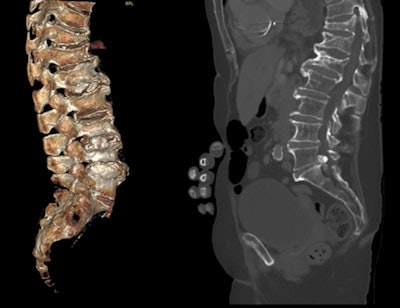

- Implement a policy of automatic sagittal spinal reformatting and display and storage on PACS for cross-sectional imaging studies that include the spine.

- Consider a policy for template reporting of cross-sectional imaging studies that include the spine to cover bone integrity, presence of VFF, level, and grade/severity.

"Emerging AI technology and algorithms have scope to support the identification of VFFs through routine scrutiny of cross-sectional imaging via PACS and the creation of 'alert lists' of those patients with suspected VFFs. Radiological interpretation may still be required to verify absence or presence of AI-identified VFFs since this technology is currently limited in differentiating between VFFs and non-fracture deformities such as Scheuermann's disease or Schmorl's nodes," the authors stated.